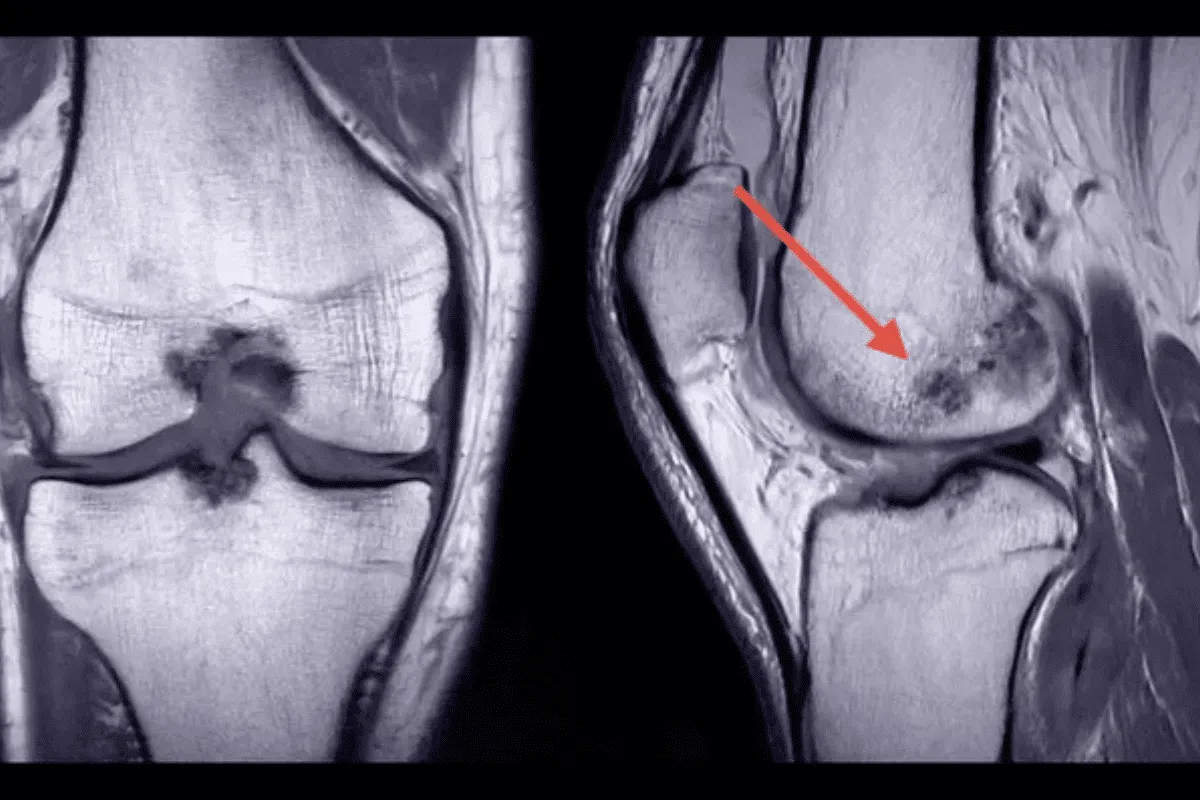

Процедура позволяет получить детальное изображение костей, суставов, кровеносных сосудов и мягких тканей.

КТ сканирование имеет преимущества перед другими методами. Оно дает более детальные снимки, чем рентген. КТ исследует как кости, так и мягкие ткани, что делает его универсальным. В отличие от МРТ, КТ лучше показывает кости и кальцификаты.

КТ сканирование ног дает точные диагнозы. Оно показывает детали ног, помогая выявлять болезни и травмы.

КТ сканирование ног очень чувствителен и специфичен. Это значит, что он точно показывает, есть ли болезнь или нет. Он может обнаружить даже небольшие изменения в ноге.

Например, при травмах КТ сканирование точно показывает переломы и смещения. Это важно для срочной помощи.

КТ сканирование ног лучше, чем рентген или МРТ. Рентген быстрый, но не такой детальный. МРТ показывает мягкие ткани, но хуже костные.

КТ сканирование идеально сочетает в себе детальность для всех тканей. Это делает его неотъемлемым инструментом для диагностики ног.